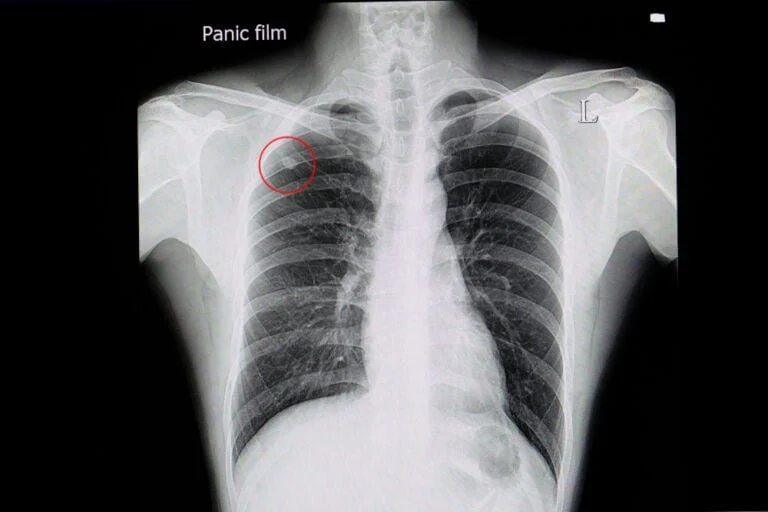

Os nódulos pulmonares normalmente são benignos, mas sempre demandam investigação para eliminar a possibilidade de câncer de pulmão

Nódulo pulmonar é um termo amplo que diz respeito a alterações radiológicas detectadas em exames de imagem que abrangem o pulmão, podendo apresentar-se como uma lesão circular ou de limites imprecisos localizada em um dos pulmões. De maneira sistematizada, nódulos tem até 3 cm, sendo que acima deste tamanho define-se como massa pulmonar.

Por se tratar de uma condição que geralmente é assintomática, a maior parte dos nódulos de pulmão é identificada quando o paciente se submete a exames de rotina (check up) ou durante a investigação de outras condições de saúde. O exame de imagem mais importante para avaliar um nódulo pulmonar é a tomografia computadorizada de tórax. Com base nas características da imagem, o médico especialista (cirurgião de tórax ou pneumologista) avalia o risco de câncer pulmonar e conduz a investigação a respeito da alteração. Em casos específicos, pode ser necessário realizar uma biópsia do nódulo para confirmação diagnóstica.